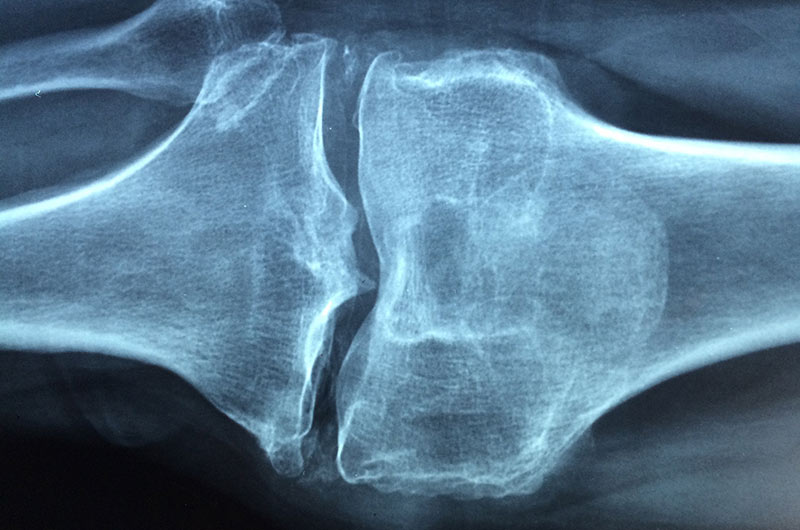

Osteoporose („Knochenschwund“) ist eine weit verbreitete Volkskrankheit – und eine der meist unterschätzten! Laut Weltgesundheitsorganisation WHO ist Osteoporose eine der zehn wichtigsten Volkskrankheiten der Welt.

Das Knochen- oder Skelettalter deckt sich normalerweise mit dem chronologischen Alter eines Kindes oder Jugendlichen. Bei Entwicklungsstörungen (z.B. Hoch- oder Kleinwuchs) kann das Knochenalter vom tatsächlichen Alter abweichen. Für eine Behandlung ist die Bestimmung des Skelettalters notwendig.